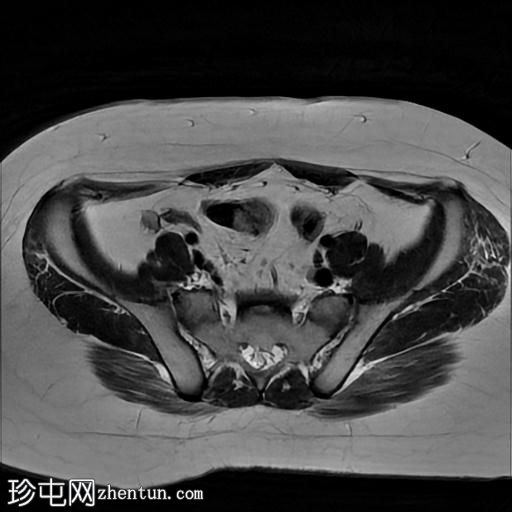

3.jpg

轴位T2

脂肪饱和度

MRI序列显示:

女性外生殖器

子宫、宫颈及阴道上2/3缺失

左侧睾丸及腹股沟管内环

右侧睾丸位于腹腔内,靠近腰大肌

双侧卵巢未显影

MRI结果提示雄激素不敏感综合征 (AIS),患者基因构成为男性,但外生殖器为女性(46XY核型)。由于细胞对睾酮等雄激素产生抵抗,雄激素不敏感综合征常伴有双侧隐睾。

区分雄激素不敏感综合征与Mayer-Rokitansky-Küster-Hauser综合征(MRKH)至关重要。MRKH综合征具有女性核型,女性外生殖器和卵巢正常,但子宫缺失或发育不全。